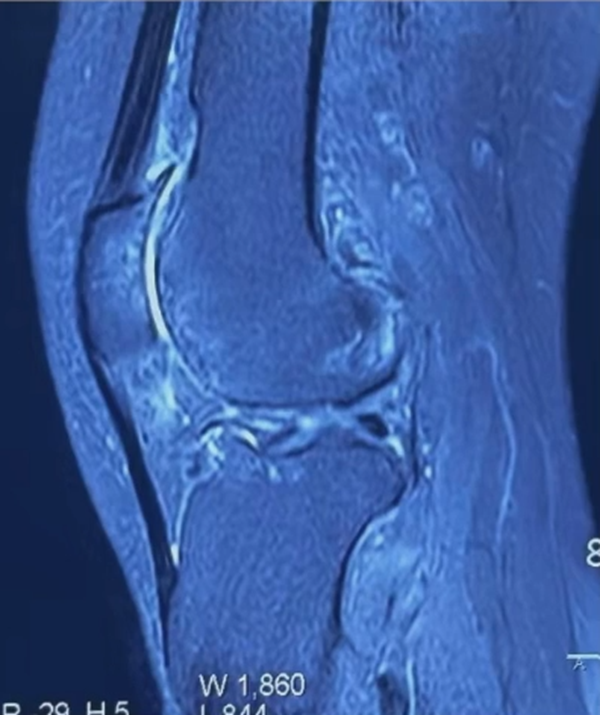

术前MRI显示:软骨破坏,形成骨磨骨。

术前MRI